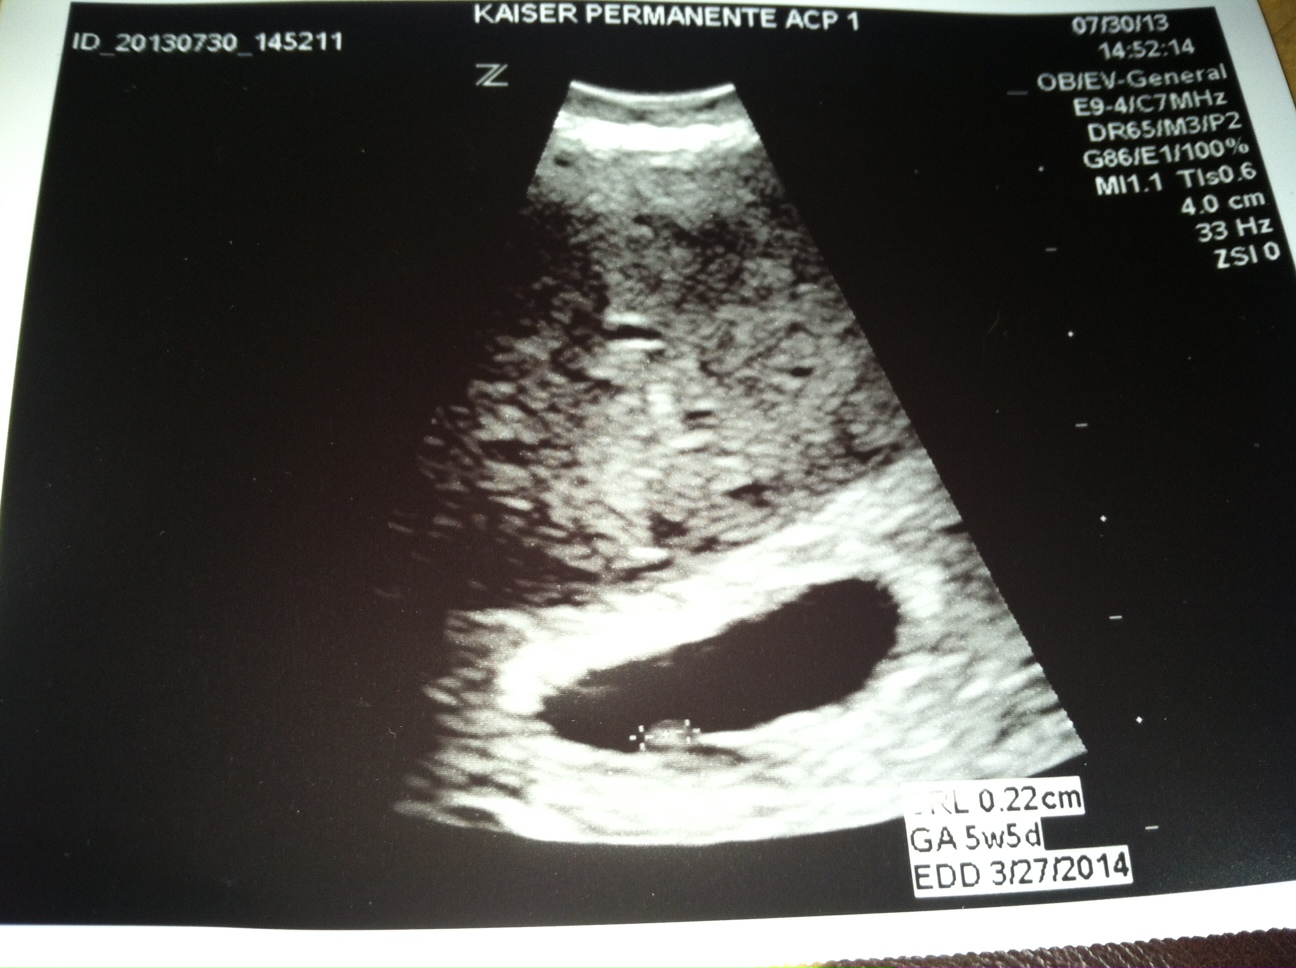

First U/S

Measured one week early because of cycle and ovulated late. Second ultrasound is on tuesday. I should be 7 weeks and 6 days.

Ultrasound: 5 weeks and 5 days